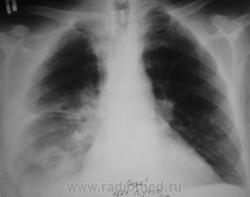

Пациенту в "области" была произведена операция по поводу "аденомы" предстательной железы. Через 3 дня после операции состояние пациента резко ущудшилось, была назначена рентгенография. Снимок ниже.

Валентин Львович! Наверняка перед операцией пациенту выполнялась ФЛГ и там возрастная норма (надеюсь, что это так). Следовательно "аденома" не является причиной изменений в легких. Тогда остается холодная операционная и абсцедирующая пневмония правого легкого.

До операции - "норма".

Но все таки абсцедирующая пневмония!

Думаю, что да - это абсцесс легкого

Объясните мне, не специалисту в пульмонологии, может ли абсцесс сформироваться за 3 дня. Или я что-то не так поняла? Видна дренированная полость, округлая, довольно четко отграниченная. В плевральной полости жидкость.

Уважаемая Nela! Двайте пойдем "логическим путем"(надеюсь, что вместе). Пожилой пациент готовится к плановой операции (аденомэктомии). Насколько мы знаем организацию нашего здравоохранения, перед плановой операцией пациент в амбулаторном порядке проходит кучу предоперационых исследований (анализы крови, мочи, ЭКГ, УЗИ простаты, почек, ФЛГ и т.д.). Если все в порядке и противопоказаний к оперативному вмешательству не имеется, пациента берут на операцию. Если имеются малейшие отклонения - то до их устранения. Если противопоказания не устранимы - пациенту в плановой операции может быть отказано. Пациента на операцию взяли, т.е. все в порядке, в том числе и в легких. Через три дня после операции мы видим представленную рентгенологическую картину. Деструкция легочной ткани. Абсцедирующая пневмония, абсцесс легкого. Смею Вас заверить, по собственному опыту, и у пациентов зрелого возраста и у молодых пациентов в послеоперационном периоде (3-5 дней) возможно развитие осложнения послеоперационного периода в виде пневмоний, в том числе абсцедирующих. Причина - чаще всего внутрибольничный стафилококк. Операция - ослабление иммунитета- внутрибольничная (очень злая, доморощенная, устойчивая к антибиотикам) стафилококковая инфекция. Вот и  пришли к конечной точке нашего пути.